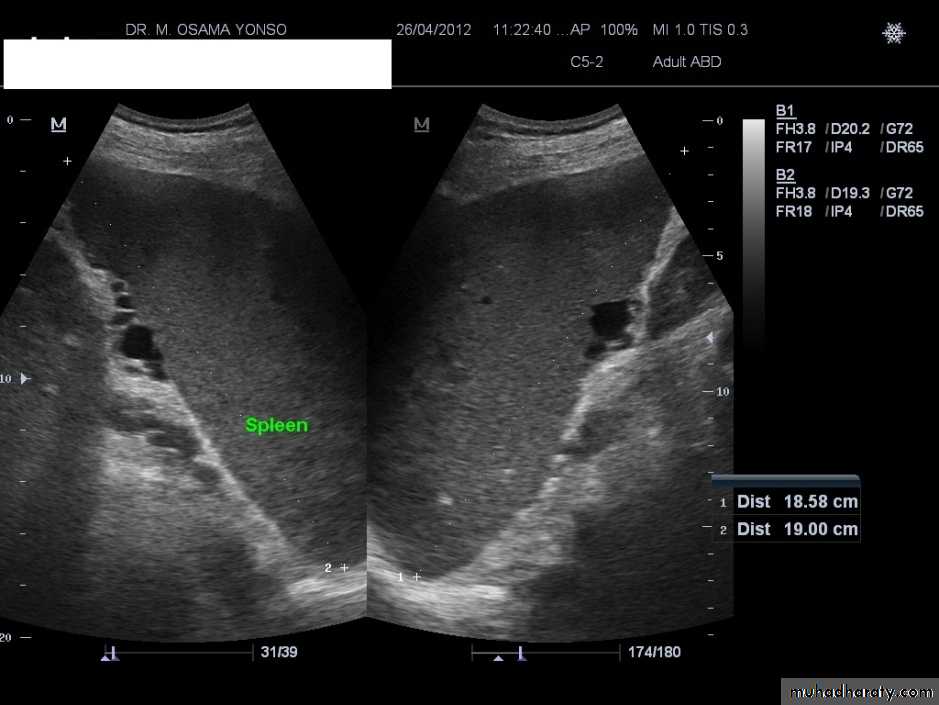

Spleen

CT

MRI

Splenic injurypancreas